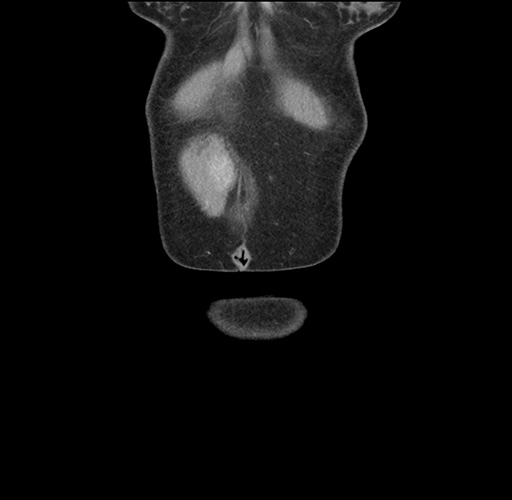

Imaging Analysis

Look through the patient's CT scan to identify any areas of concern for the necessary procedure.

Based on your CT findings, which issue(s) would give reason for "planned slowing down moment(s)" in this case?

Considering a standard left lateral sectionectomy procedure, what step(s) of the operation would you do differently in this case ?